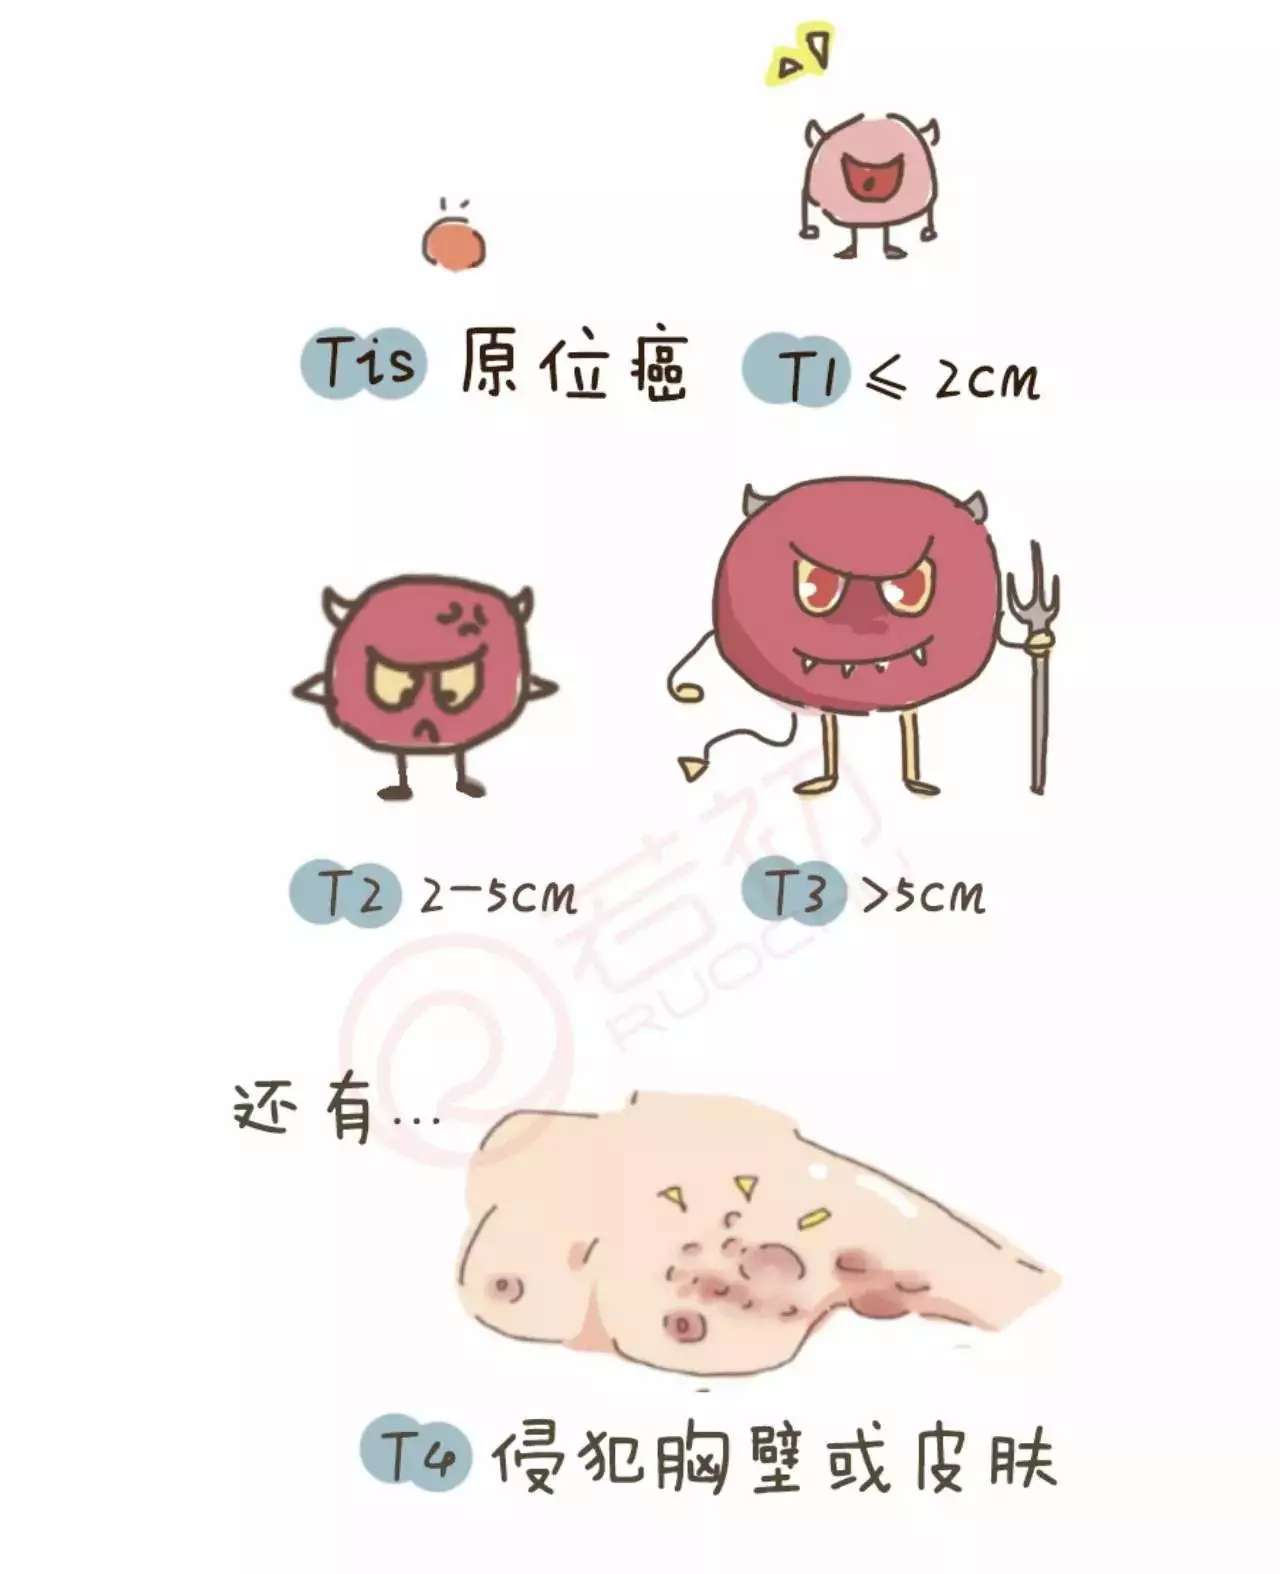

“高危”or”低危”,乳腺癌患者复发风险如何评估?-乳腺癌康复圈-觅健